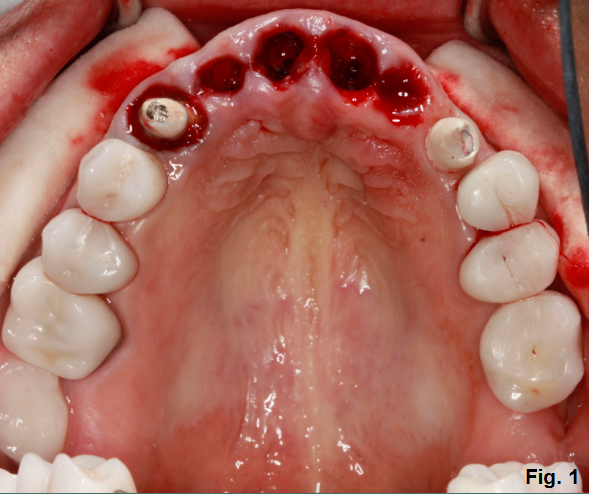

This patient has decided to have his upper maxillary incisors removed following a significant dental history that includes endodontic treatment, clinical crown lengthening, full coverage restorations and trauma. (Fig. 1)

Fresh extraction sites visible in the photos certainly lead to the question as to whether or not the labial plate of bone is intact or fractured for each of the incisors. Will augmentation or grafting be indicated and how will that impact the provisional restoration? What about lip length and lip mobility particularly as it pertains to gingival display?

What types of discussion items would be important for the patient to know prior to this point? What would you like to know based on what you see in the clinical photo?